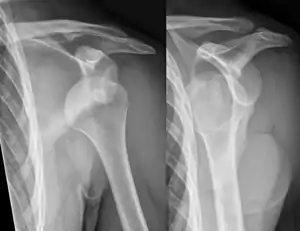

A diagnosis of shoulder dislocation is often suspected based on the person's history and physical examination. Radiographs are made to confirm the diagnosis. Most dislocations are apparent on radiographs showing incongruence of the glenohumeral joint. Posterior dislocations may be hard to detect on standard AP radiographs, but are more readily detected on other views. After reduction, radiographs are usually repeated to confirm successful reduction and to detect bone damage. After repeated shoulder dislocations, an MRI scan may be used to assess soft tissue damage. In regards to recurrent dislocations, the apprehension test (anterior instability) and sulcus sign (inferior instability) are useful methods for determining predisposition to future dislocation.

A shoulder dislocation often occurs as a result of a fall onto an outstretched arm or onto the shoulder.[3] Diagnosis is typically based on symptoms and confirmed by X-rays.[2] They are classified as anterior, posterior, inferior, and superior with most being anterior.[2][1]

Treatment is by shoulder reduction which may be accomplished by a number of techniques.[1] These include traction-countertraction, external rotation, scapular manipulation, and the Stimson technique.[1] After reduction X-rays are recommended for verification.[1] The arm may then be placed in a sling for a few weeks.[2] Surgery may be recommended in those with recurrent dislocations.[2]